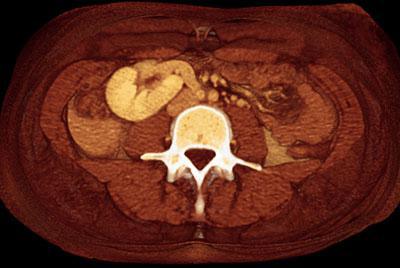

Ectopia renal homolateral: riñón ectópico en el mismo lado que el uréter correspondiente: craneal, abdominal, ilíaco o pélvico

Ectopia renal cruzada: el riñón está situado en el lado opuesto a su orificio ureteral correspondiente.

Así mismo puede estar fusionado o no al riñon ortotópico. Habitualmente se fusionan el polo superior del riñón ectópico con el polo inferior del riñón ortotópico El uréter del riñón ectopico debe cruzar la linea media para alcanzar el meato ureteral correspondiente El riñón ectópico habitualmente presenta una anomalía de rotación Es muy importante conocer el origen arterial y el drenaje venoso de este riñón ectópico